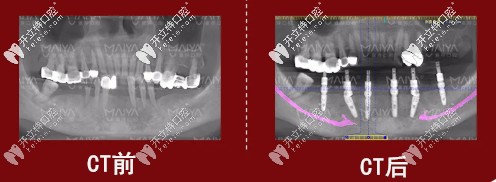

種植前后對(duì)比圖

去年是先做了下半口,拔掉6顆牙。醫(yī)生根據(jù)我剩余牙齒情況,所以特別給我設(shè)計(jì)的是ALL-on-6,給我保留能保留的牙齒,只需要種6顆恢復(fù)半口牙,當(dāng)天種牙當(dāng)天即可正常吃飯,吃牛肉,咬蘋(píng)果都沒(méi)問(wèn)題。(之前以為都是廣告宣傳,哪有當(dāng)天種當(dāng)天就能啃蘋(píng)果,現(xiàn)在我是真信了~)

種植牙前后對(duì)比圖

之所以選擇用瑞典諾貝爾種植體做all-on-6即刻負(fù)重,是因?yàn)橛蟹€(wěn)定性,根據(jù)不同骨質(zhì)或牙槽骨不足都可以種,重點(diǎn)是種植時(shí)間短,微小傷口,無(wú)縫對(duì)接,快速愈合。